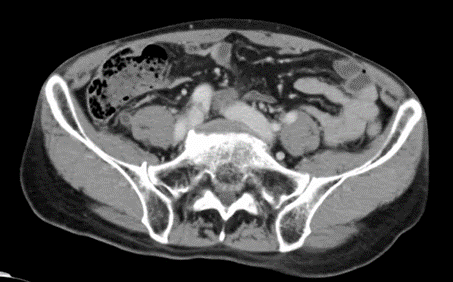

58歳男性。胸痛を訴えていたが、心血管疾患は否定的で、胸腹部造影CT施行。

所見としては虫垂に腫大と周囲脂肪織濃度の上昇。

診断:急性虫垂炎